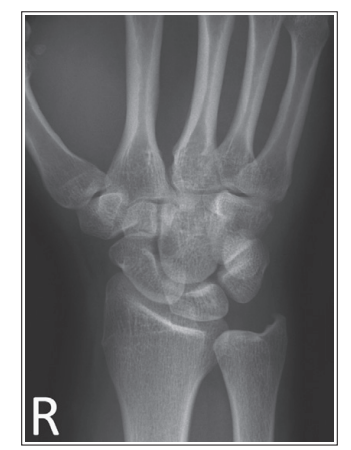

What is wrong with this oblique wrist xray

Under-rotated

Less than 45 degree obliquity

5th shaft of MC is in profile

External rotation

Shaft of thumb MC is if profile

Internal rotation